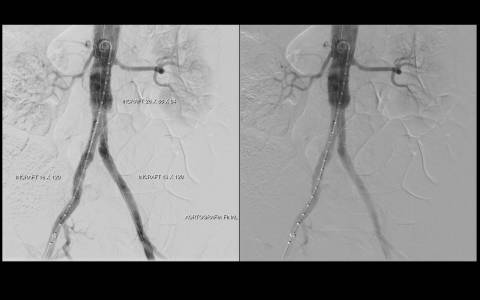

TRATAMENTO ENDOVASCULAR DE HEMATOMA INTRAMURAL DA AORTA ABDOMINAL COM ENDOPRÓTESE DE BAIXO PERFIL

Paciente da entrada hospitalar com dor cardíaca típica sendo diagnosticado com infarto agudo do miocárdio em dezembro de 2019. Apresentava passado de outros três episódios e de revascularização cardíaca com mamária e ponte de safena. Durante internamento paciente evolui com dor abdominal importante sendo indicada realização de tomografia de abdome total que indicou a presença de hematoma intramural da aorta abdominal.

Haja vista a extensa quantidade de comorbidades a cirurgia aberta se fazia de risco muito elevado para o paciente. Este foi então encaminhado para correção endovascular.

O estudo de angiotomografia evidenciou que as artérias iliacas externas e femorais apresentavam-se com muitas calcificações e ponto de estenose mais crítica em artéria ilíaca comum direita. Diante dos achados de imagem, foi optado por endoprotese de aorta abdominal de baixo perfil (Incraft – Cordis).